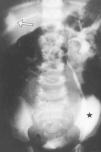

Objetivo: Ilustrar el espectro de hallazgos radiológicos de las duplicaciones del tracto urinario y mostrar la eficacia de los ultrasonidos, la cistouretrografía miccional seriada (CUMS), la urografía intravenosa (UIV), el estudio isotópico y la resonancia magnética (RM) en el manejo de estas entidades. Material y métodos: Hemos revisado retrospectivamente los hallazgos radiológicos de las duplicaciones del riñón, uréter, vejiga y uretra a partir de los datos de nuestro archivo de patología genitourinaria pediátrica. Todos los casos cuentan con estudio ecográfico, mientras que la CUMS, la UIV, el estudio isotópico y la RM se realizaron en función del tipo de duplicación. Hacemos hincapié en las bases embriológicas de los hallazgos radiológicos que, cuando fue posible, se cotejaron con los hallazgos anatomopatológicos. Resultados: Las duplicaciones completas o incompletas afectaron con más frecuencia al sistema pielocalicial y al uréter (pelvis renal bífida, uréter semibífido, uréter bífido bajo, duplicación ureteral completa y triplicación). Las duplicaciones vesicales se muestran en los planos sagital y coronal, aunque la forma más frecuente fue la división sagital con dos vejigas resultantes contiguas separadas por un pliegue peritoneal con tejido areolar fino. Las duplicaciones uretrales o las uretras accesorias se dieron fundamentalmente en el plano coronal; sin embargo, también describimos la duplicación en el plano sagital en ausencia de duplicación vesical. Mostramos un caso extremadamente raro de duplicación completa de uretra femenina. Conclusión: Mostramos una visión de conjunto de las duplicaciones del tracto urinario y discutimos la utilidad de varias técnicas de imagen disponibles. Dado que estas entidades tienen una apariencia radiológica característica, este artículo puede ser útil para comprender mejor estas anomalías.

Objective: To illustrate the spectrum of imaging findings for urinary tract duplications and to show the efficacy of ultrasonography (US), voiding cystourethrography (VCU), intravenous urography (IVU), scintigraphy, and magnetic resonance (MR) in the management of these entities. Material and methods: We have reviewed the imaging findings for cases of renal, ureteral, vesical, and/or urethral duplication from our pediatric genitourinary pathology archive. All patients underwent US examination; VCU, IVU, scintigraphy, and MR studies were performed in function of the type of duplication. We explain our findings within the framework of embryological development and correlate the imaging findings with the histopathologic findings whenever possible. Results: Complete or partial duplications most commonly affected the pyelocalyceal system or the ureters (bifid renal pelvis, bifid mid-ureter, low bifid ureter, complete ureteral duplication and triplication). Vesical duplications are shown in the sagittal and coronal planes, although the most common presentation was sagittal division resulting in two contiguous bladders separated by a peritoneal fold with thin areolar tissue. Ureteral duplication or accessory ureters were mostly seen in the coronal plane; however, we also describe duplication in the sagittal plane in the absence of vesical duplication. We show an extremely rare case of complete duplication of the female urethra. Conclusion: We provide an overview of the set of urinary tract duplications and discuss the usefulness of the different imaging techniques available for each type. As these entities have a typical radiological appearance, this article can help to understand these anomalies better.